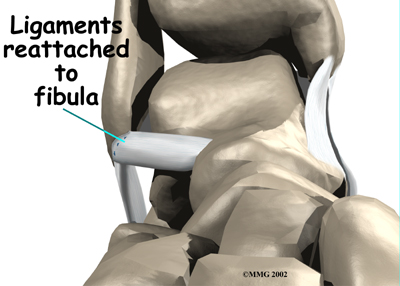

Ligament Tightening Procedure

Chronic ankle instability can happen when the lateral ankle ligaments are stretched or torn and the ankle keeps giving way. Surgery can be done to tighten the stretched ligaments and improve the stability of the ankle. The surgery usually involves the ATFL and the CFL.

In this procedure, an incision is made in the skin that lies over the lateral ligaments. Using a scalpel, the surgeon cuts the ATFL and CFL in half.

Holes are drilled along the lower end of the fibula bone, the small bone of the lower leg. The two ends of the cut ligament are overlapped and sewn together. The surgeon uses the drill holes in the fibula to hold the stitches to the bone.

A large band of connective tissue crosses the front of the ankle just below the lateral ligaments. This band, called the ankle retinaculum, holds the tendons in place. The surgeon pulls the top edge of the ankle retinaculum upward and sews it into the fibula. This helps reinforce the reconstructed ligaments.

The following images show each step of the ligament tightening procedure:

Step 1

Step 2

Step 3

Step 3

Step 4